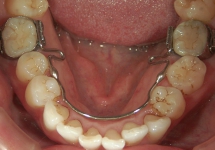

バイヘリックス(BH)

QHと同じく顎の骨幅を広げる効果があり、歯列の幅が広がります。ヘリカルループというワイヤーのくるくるが2つのため、QHよりも力は弱いですが、舌がある下顎には、かさばらないBHを使用します。